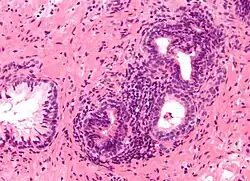

Micrograph of benign prostatic glands with corpora amylacea. H&E stain.

The prostate consists of glandular and connective tissue.[2] Tall column-shaped cells form the lining (the epithelium) of the glands.[2] These form one layer or may be pseudostratified.[4] The epithelium is highly variable and areas of low cuboidal or flat cells can also be present, with transitional epithelium in the outer regions of the longer ducts.[10] Basal cells surround the luminal epithelial cells in benign glands. The glands are formed as many follicles, which drain into canals and subsequently 12–20 main ducts, These in turn drain into the urethra as it passes through the prostate.[4] There are also a small amount of flat cells, which sit next to the basement membranes of glands, and act as stem cells.[2]

The connective tissue of the prostate is made up of fibrous tissue and smooth muscle.[2] The fibrous tissue separates the gland into lobules.[2] It also sits between the glands and is composed of randomly orientated smooth-muscle bundles that are continuous with the bladder.[11]

Over time, thickened secretions called corpora amylacea accumulate in the gland.[2]